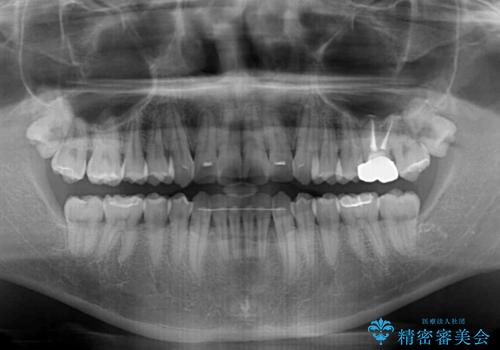

- 前歯のデコボコを治したいとのことで来院された患者様です。

上下顎ともに歯列全体の後方移動とIPR(歯と歯の間を削る)によってデコボコが解消するように設計し、インビザラインにより治療を行うこととしました。

毎日22時間以上しっかりとマウスピースを装着していただいたので、スムーズに治療が進みました。歯と歯の間を削ることでうまくスペースコントロールでき、1年強で終えることができました。